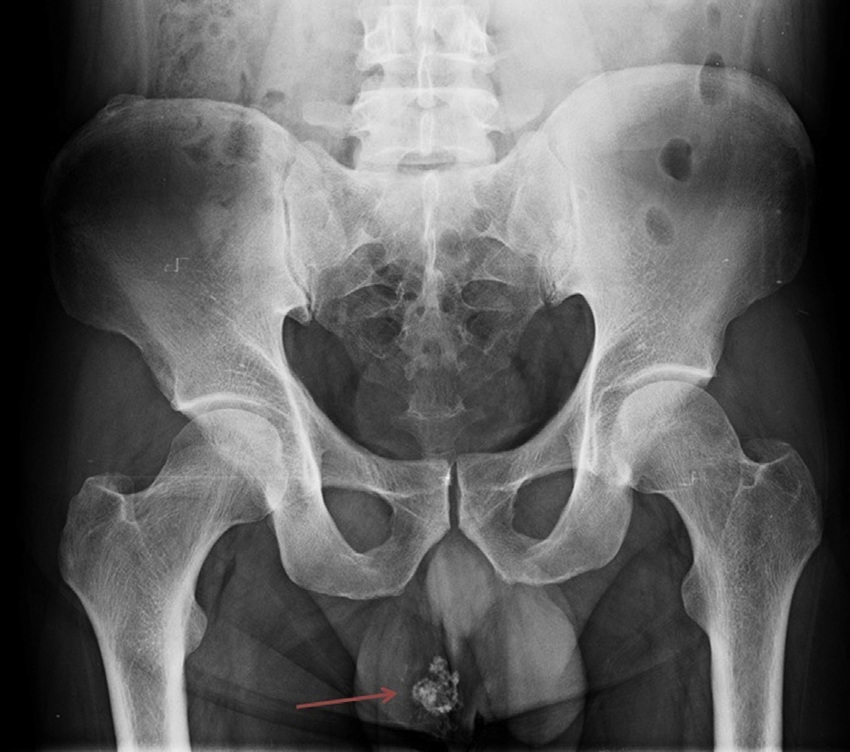

É um dente (sim, já acharam dente crescendo lá)